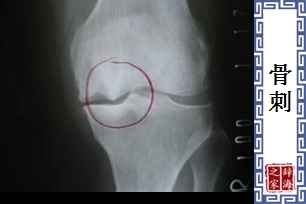

- 因骨头退化、变形而突长的刺状物。在腰椎最常见,常引起疼痛与关节活动不灵活等症状。

【骨刺】 图片鉴赏